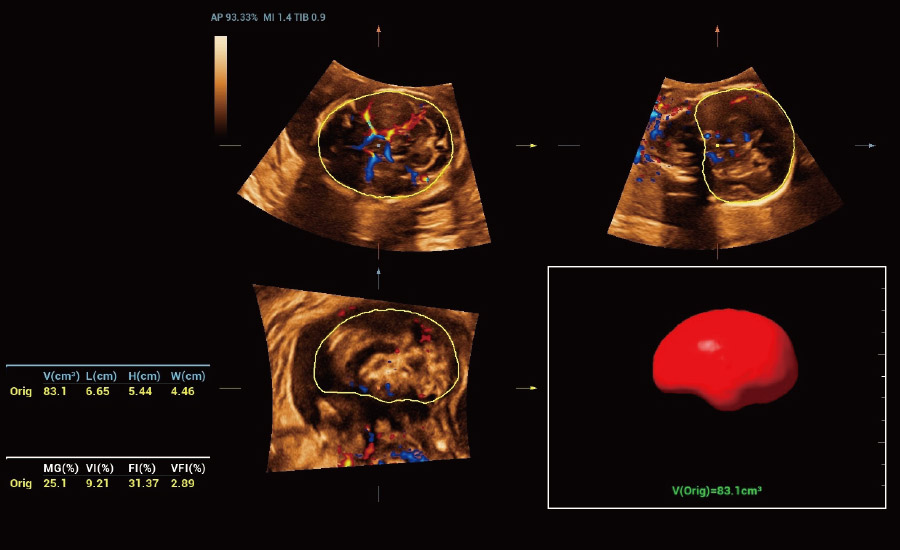

Explore mais detalhes e realidade escondida

UMA (angiografia ultramicroscĆ³pica)

A tecnologia inovadora elimina as limita??es das tradicionais imagens com Doppler. Com resolu??o espacial e sensibilidade de fluxo ultra-altas, permite a detec??o de perfus?es de fluxos muito sutis e lentos, ampliando assim a aplica??o clĆnica da avalia??o qualitativa e quantitativa do ultrassom no cĆ©rebro fetal, rins, placentas, endomĆ©trios, ovĆ”rios etc.

UMA 3D ā Fluxo sanguĆneo perifolicular

Informa??es abrangentes adaptadas aos cenƔrios

Por meio da combina??o de algoritmos avan?ados e do conhecimento especĆfico da regi?o, a inovadora solu??o Smart Scene permite a identifica??o automĆ”tica das caracterĆsticas do tecido e fornece diagnĆ³stico especĆfico dos Ć³rg?os com informa??es completas. Com base na identifica??o automĆ”tica de cenĆ”rios, a solu??o realiza n?o apenas a varredura 2D inteligente com configura??es e medidas automĆ”ticas, mas tambĆ©m oferece informa??es 3D abrangentes em todas as etapas, desde a otimiza??o de imagens volumĆ©tricas atĆ© a difĆcil obten??o de planos 2D, e a quantifica??o durante todo o procedimento. Ele ajuda a reduzir em grande parte a dependĆŖncia de habilidades clĆnicas, ao mesmo tempo que aumenta a precis?o, a confian?a e a eficiĆŖncia no diagnĆ³stico.